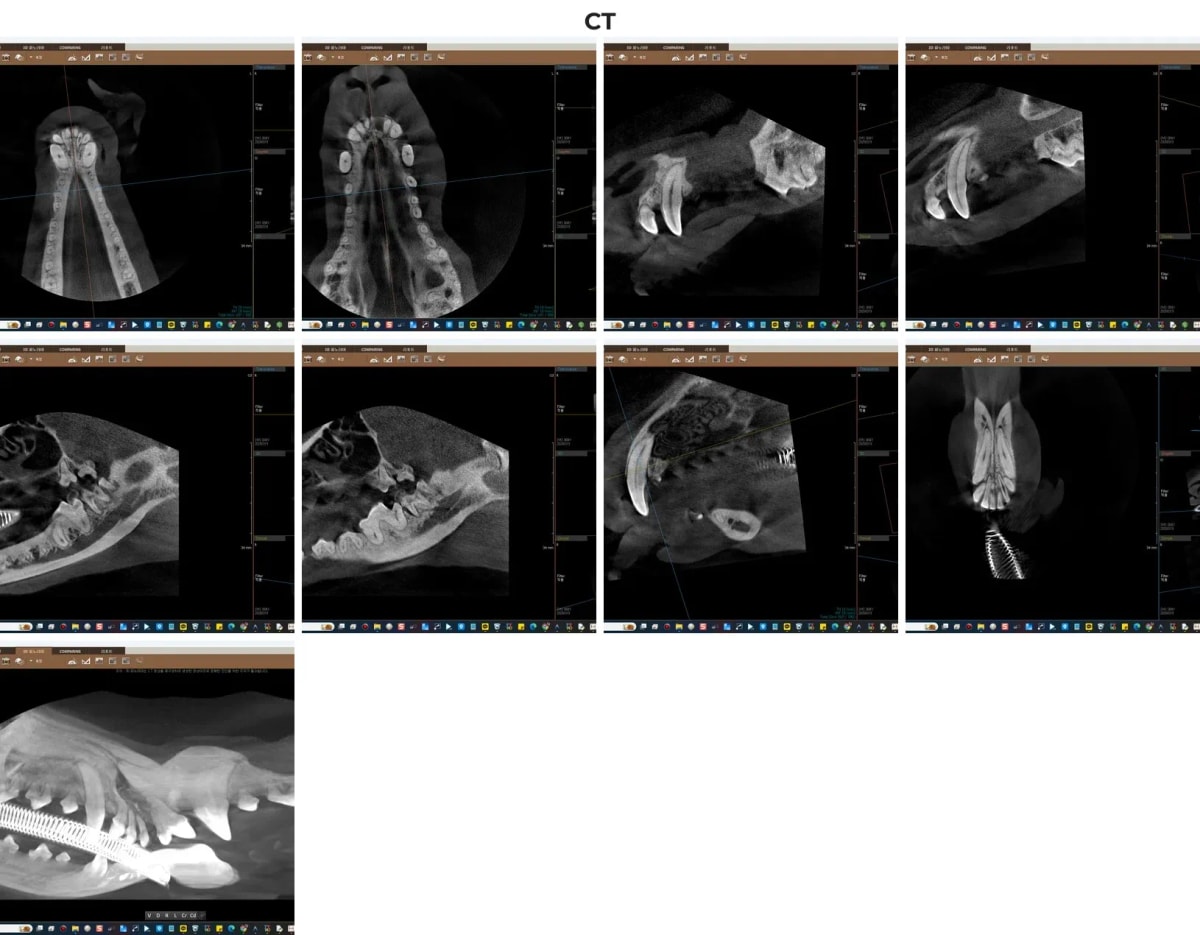

2. 진단: 광주·전남 유일 치과 전용 CT의 결정적 역할

일반 구강 방사선만으로는 치아 뿌리가 3차원적으로 어떻게 뼈와 얽혀 있는지, 그리고 염증이 어느 방향으로 뼈를 녹이고 있는지 완벽하게 파악하기 어렵습니다. 본원은 광주·전남 유일의 치과 전용 CT를 도입하여 0.1mm 단위의 미세 병변까지 입체적으로 구현, 신경과 혈관 손상을 완벽히 차단하는 안전한 수술 계획을 수립합니다.

루피의 치과 CT 정밀 스캔 화면

CT 판독 결과, 상악 앞니(101번)의 치조골 흡수뿐만 아니라, 보호자님이 인지하지 못하셨던 하악 좌우 안쪽 어금니(310, 311, 410, 411번) 부위에서 심각한 치조골 소실이 발견되었습니다. 핵심 치아인 9번 어금니의 치조골에 염증이 맞닿기 직전이었기에 즉각적인 개입이 필요했습니다.